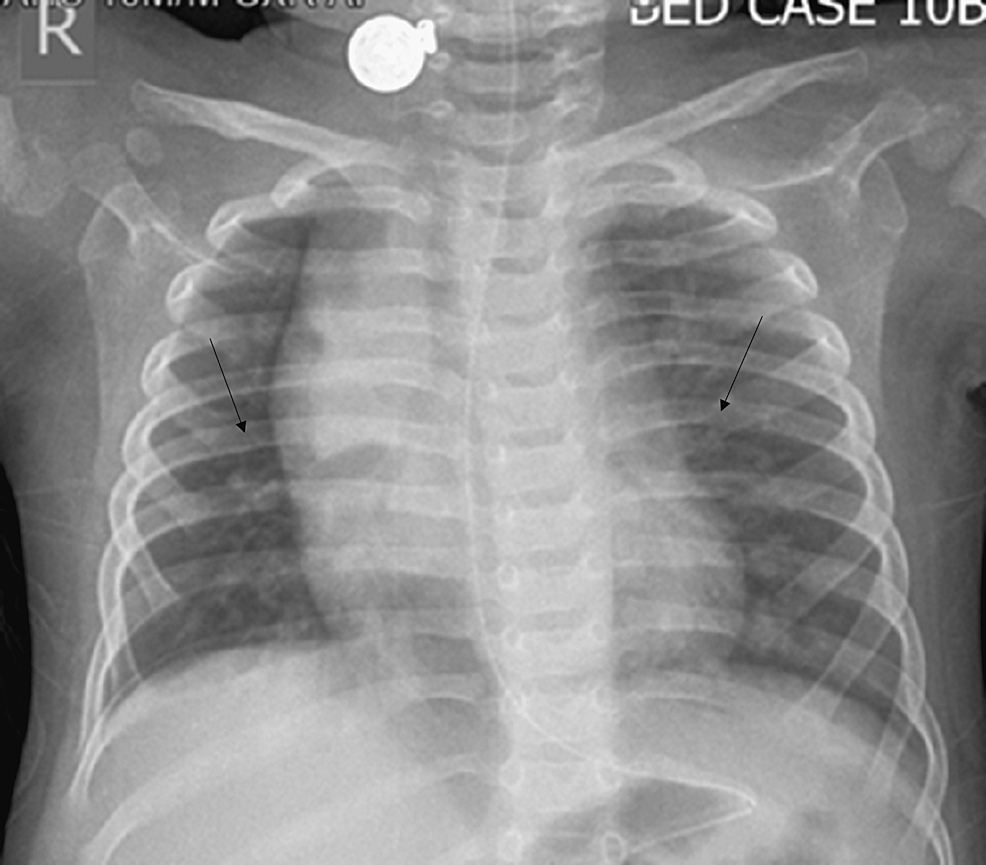

Human Adenovirus Infection Causing Hyperinflammatory Syndrome Mimicking Multisystem Inflammatory Syndrome in Children (MIS-C): A Case Report

Transmission of human adenovirus (HAdV) infection and the associated clinical disease can be sporadic or epidemic and manifestations may range from mild infection to severe disease. HAdV has been seen...

The first dose of intravenous immunoglobulins (IVIG) was administered over the course of 48 hours and the baby required a second dose of IVIG as the fever failed to settle after the first dose. Within 24 hours of the second IVIG dose, defervescence occurred. His platelet count started to rise, and the baby developed thrombocytosis in the...